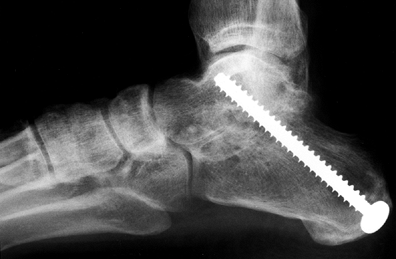

by 10 to 12 weeks (Fig. 115.4).

Figure 115.4. Radiograph demonstrating a subtalar fusion utilizing the technique described in the text.